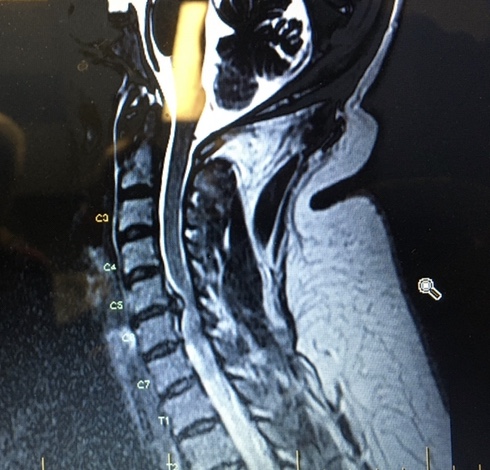

She was going to go in through the front of my throat. They would move aside my vocal chords, esophagus, thyroid, and clip them as they went to my spine in the back of my throat. She would remove all three discs impinging on my spinal cord, clean them up, and if they weren’t destroyed, replace them. But if they were destroyed, she would fuse them by drilling into the vertebrae and installing cages like trellises for the bone to grow into. It would add a centimeter to my height.

After explaining the procedure and dangers, she told me that she was surprised I had not been having symptoms for a very long time. One of the discs had been knocked into place farther than the other two, but it was kinking my spinal cord and preventing my brain from getting what it needed and doing what it needed.

“I’m surprised you haven’t been having memory problems, and difficulties with recall for even simple things like basic math or songs. This injury came from a fall that jammed your arm, knocking the discs into your spinal column, so I would have thought symptoms would have been happening for a while. She listed off seven or eight other symptoms and my body trembled as I sobbed. “You’ve been having all of them, haven’t you?”